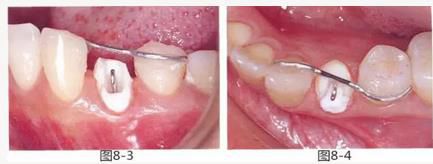

圖8-3 使用方絲和鏈狀橡皮圈,通過正畸的手段挺出牙齒。

圖8-4 使用粘接性樹脂,將S狀方絲固定在鄰牙上。

圖8-5 使用鏈狀橡皮圈進行牽引,將S狀方絲與游離牽引鉤之間的距離調(diào)整為2.5mm。